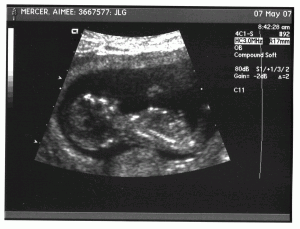

So that’s an ultrasound picture of my new darlin’ coming down the pike. Literally. Soon. She’s going to have one snookers of a time competing on the cute level with a certain spotted grumpy old bitch, big-eared-rolly-polly-round-mound-of-puppy-hound and the little man...